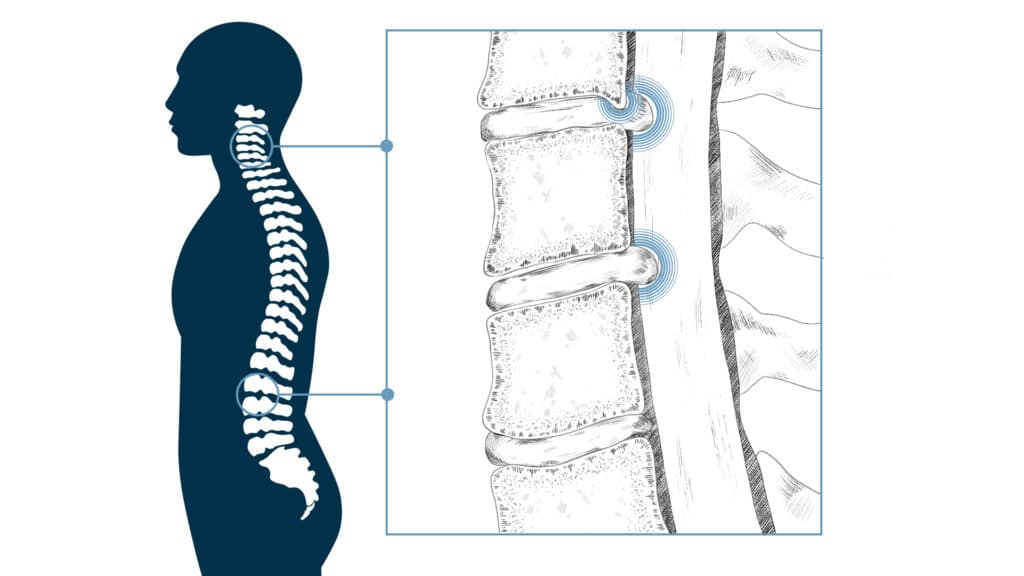

Przestrzeń nadtwardówkowa, inaczej opisywana jako przestrzeń zewnątrzoponowa, to obszar otaczający rdzeń kręgowy i nerwy, znajdujący się pomiędzy oponą twardą (najbardziej zewnętrzną warstwą opon mózgowo-rdzeniowych) a kanałem kręgowym. Podanie leku do tej przestrzeni umożliwia dotarcie leku bezpośrednio do źródła bólu, czyli w okolice nerwów oraz zmian powodujących ucisk na nerwy, takich jak wypuklina lub przepuklina krążka międzykręgowego, zmiany zwyrodnieniowe lub ciasnota kanału kręgowego. Precyzyjne podanie leków w okolice kręgosłupa pod kontrolą fluoroskopii, czyli rentgena śródoperacyjnego, to jedna z najbardziej precyzyjnych, a przez to bezpiecznych technik zwalczania zespołów bólowych kręgosłupa. W ramach Szpitala Klinicznego im. W. Degi technika ta została wprowadzona przez dr. Kubaszewskiego w 2004 roku. Zebrane doświadczenie pozwala na najbardziej optymalne zaplanowanie i przeprowadzenie leczenia.

Podanie leku do przestrzeni nadtwardówkowej jest wykonywane przez lekarza specjalistę (najczęściej anestezjologa lub neurochirurga) w warunkach ambulatoryjnych (pacjent wraca do domu tego samego dnia). Zabieg polega na wprowadzeniu igły do przestrzeni nadtwardówkowej pod kontrolą RTG (fluoroskopii), co zapewnia precyzyjne dotarcie do celu. Następnie podawany jest lek, którym najczęściej jest mieszanina kortykosteroidu (działanie przeciwzapalne) i środka znieczulającego miejscowo.